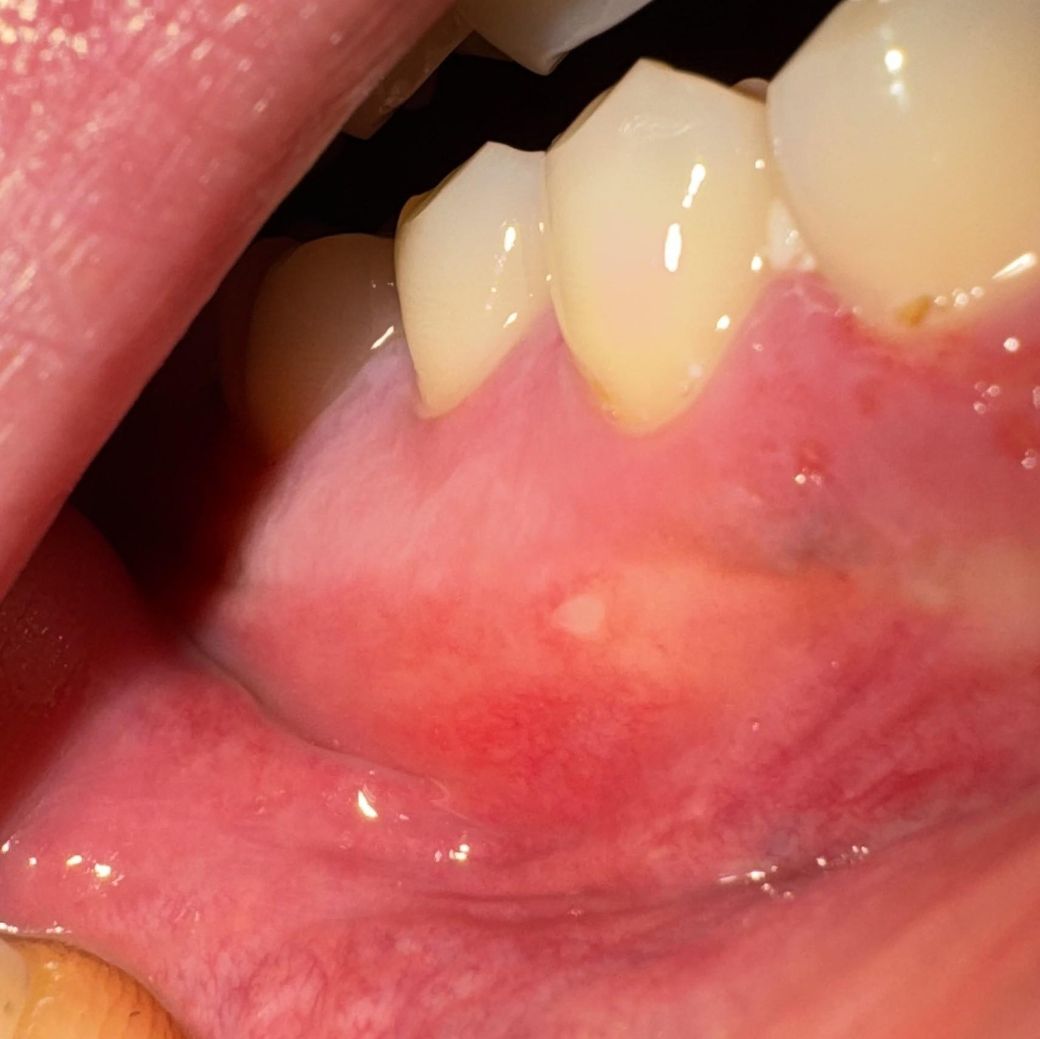

3일전쯤에 잇몸이아파서 봤더니 맨처음에는

아주조금하게 물혹(수포)? 같은게생기고 아프더라구요

그래서 그냥 냅두고 지냈더니

통증은 아직 있지만(만질때 아파요)

밥먹거나 그럴때는 많이 괜찮아진편인데

이젠 하얗게변했어요 그냥 냅두면될까요?

아니면 병원에가봐야되나요?

구내염의 양상 같습니다. 불편한 증상 있으면 약국에서 오라메디나 디프람 같은 연고 사서 바르시기 바랍니다.